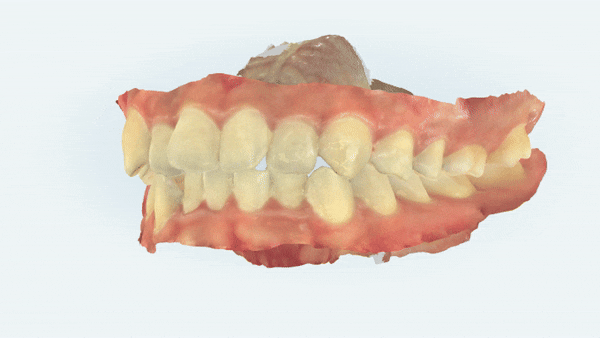

위 사진은 윗니 아랫니가 접촉되는 면을

spot 으로 나타내주는 사진 입니다.

교정 전에는

중요한 역할을 하는 송곳니가

맞물리는 치아 없이 제 기능을 하지 못하고 있었지만

교정 후

삐뚤빼뚤했던 치아들이 제 위치를 찾으며

심미적으로 개선이 되었을 뿐만아니라

송곳니 등 치아의 역할이 기능적으로 개선이 되었습니다.